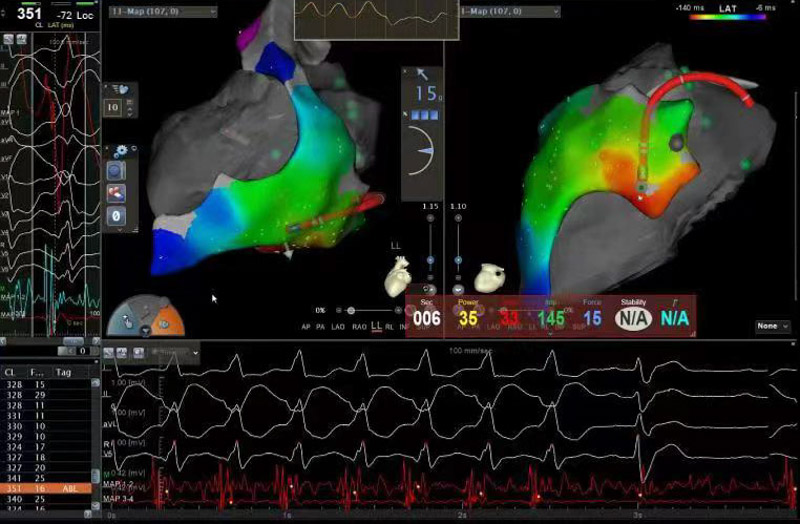

為確保手術安全,心血管內科電生理團隊準備了詳盡的手術方案和應急預案。手術當日,北京安貞醫院心血管內科蔣晨曦教授親臨指導,在ICE及X線引導下,精確地將導絲通過心包干性穿刺途徑到達心外膜,再通過動靜脈途徑到達心內膜,采用心內膜聯合心外膜進行標測及消融。放電3秒后室性心動過速終止,鞏固消融120秒,并在靶點附近鞏固放電多次,經過一段時間觀察,無室性心動過速再發,手術順利結束。術后患者癥狀解除,復查動態心電圖顯示無室性心律失常再發,目前陶先生已成功康復出院,門診隨訪也一切良好。